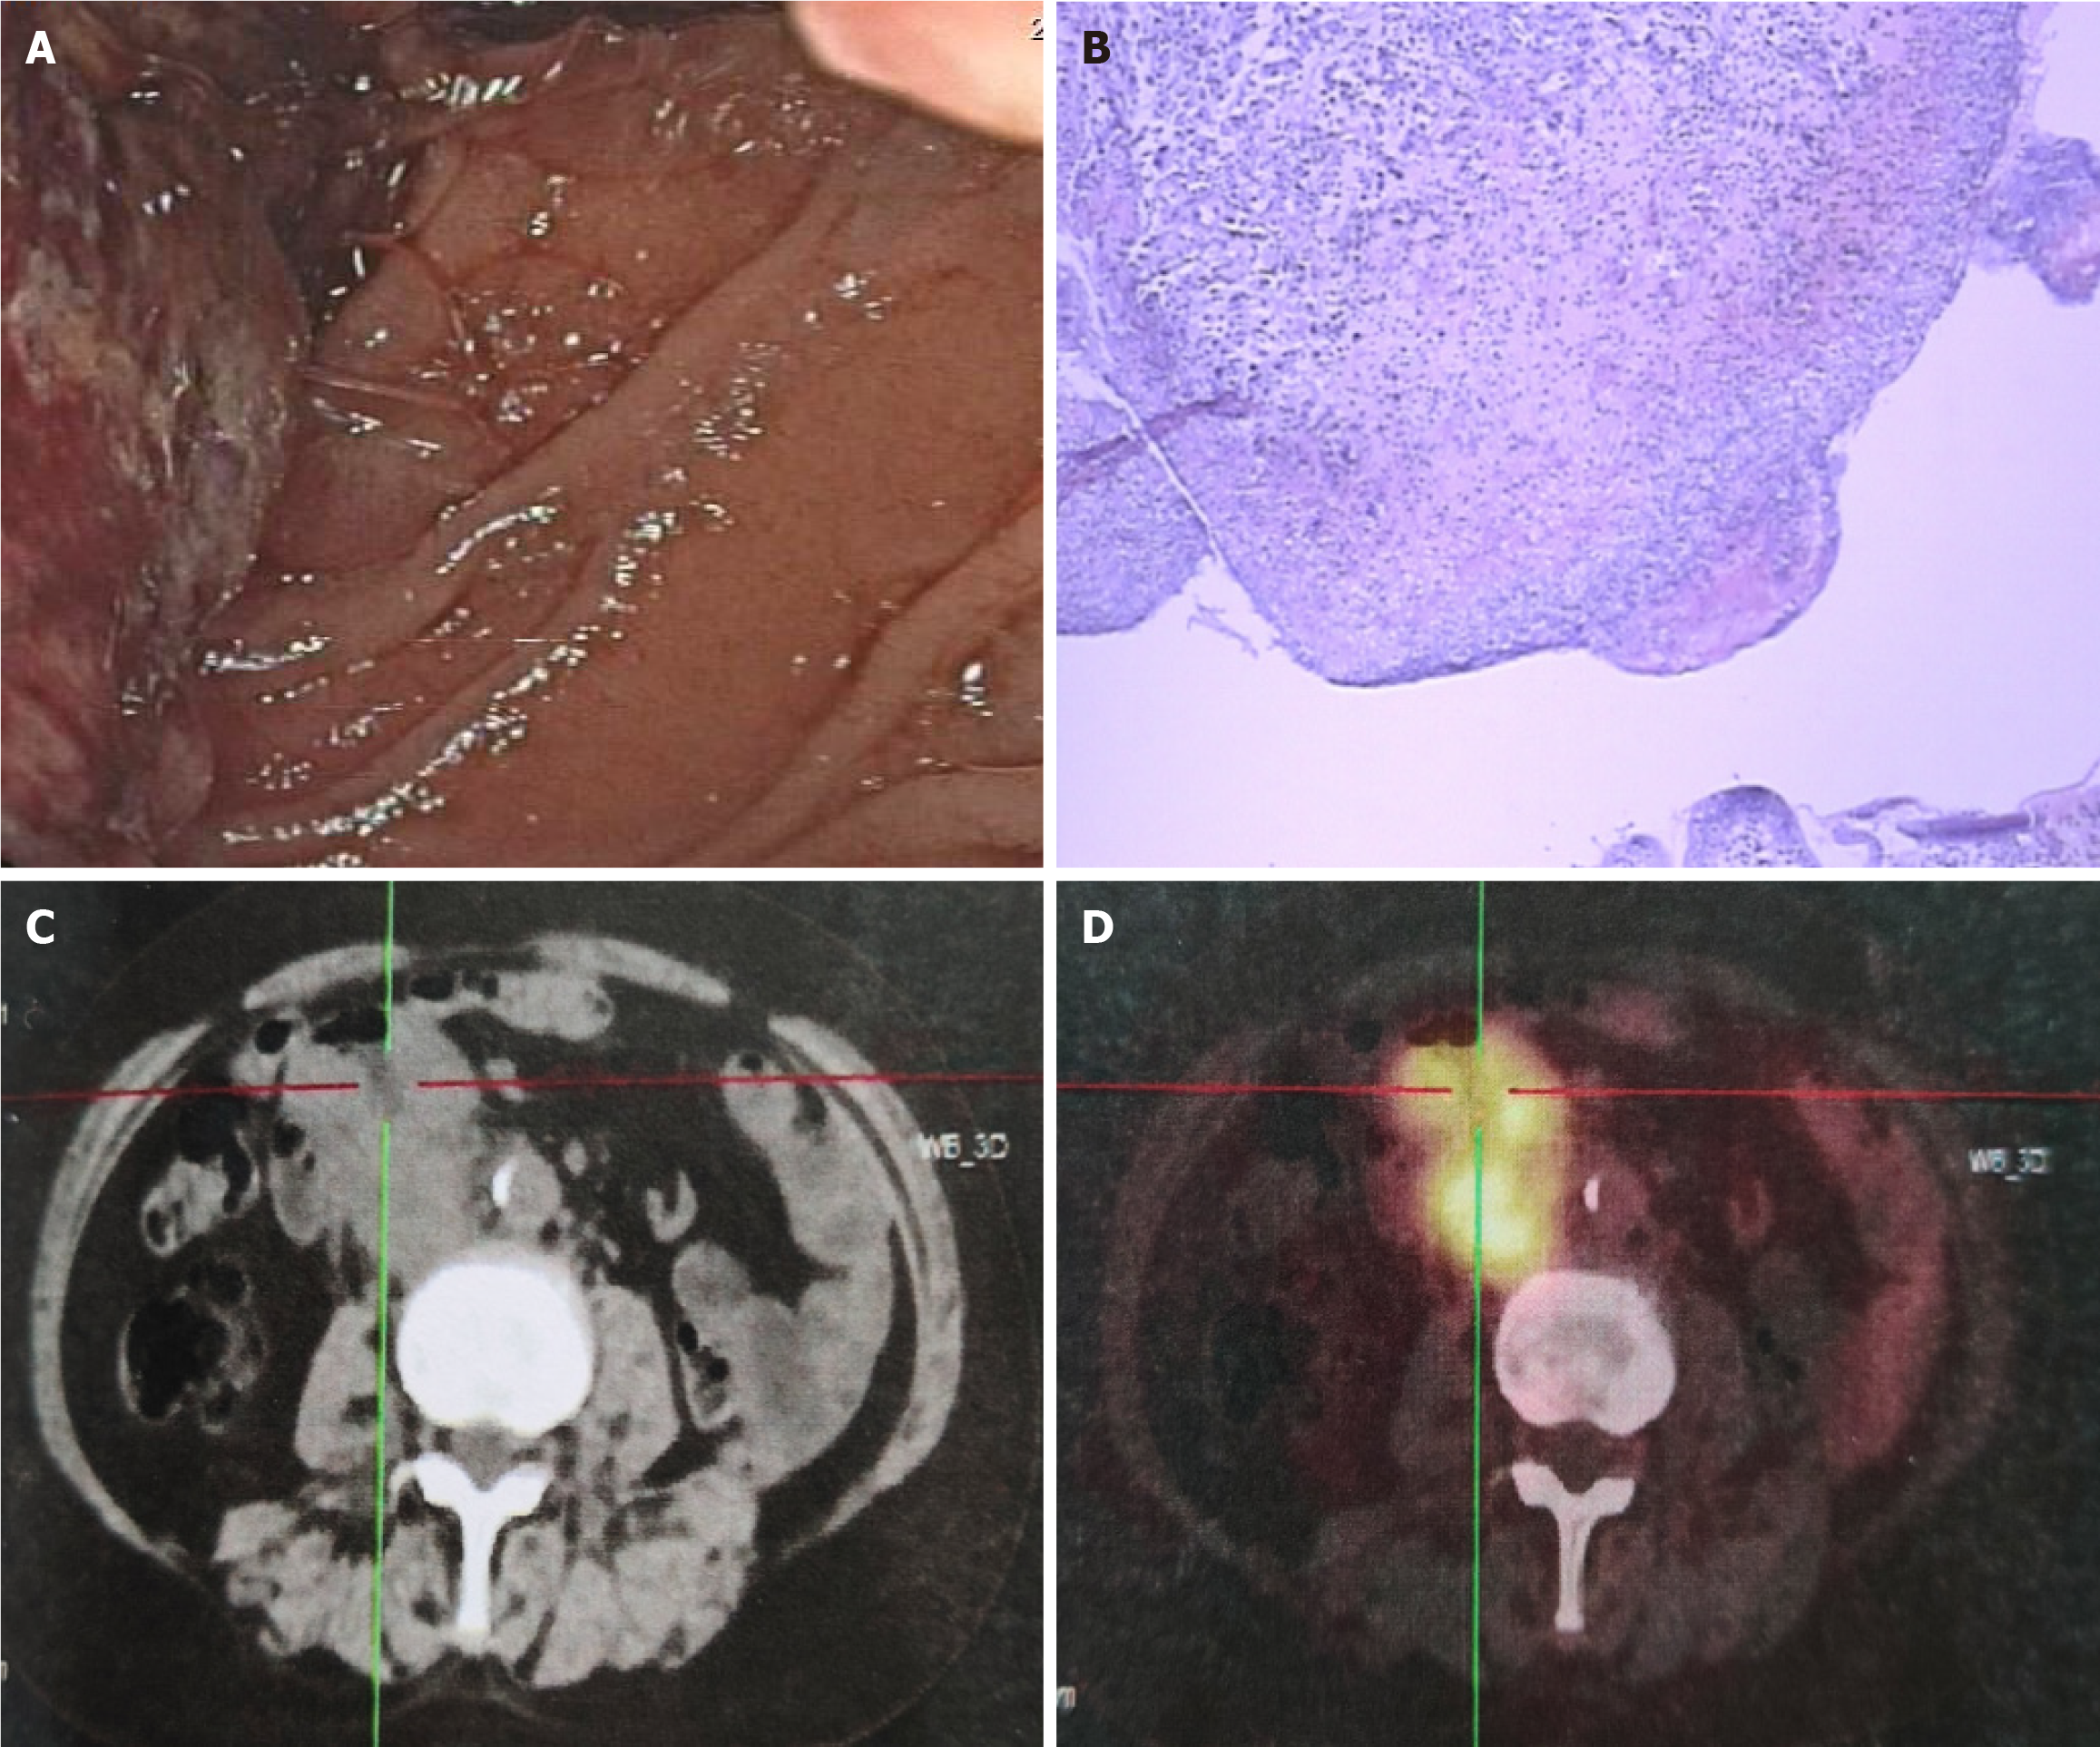

Figure 1 Before receiving chemotherapy.

A: Upper gastrointestinal endoscopy showed a mass in the descending duodenum with bleeding; B: Hematoxylin-eosin staining showed adenocarcinoma; C and D: Positron emission tomography/computed tomography examination showed uptake of 18F-fluorodeoxyglucose in the descending and horizontal segments of the duodenum, around the intestinal wall, and retroperitoneum.